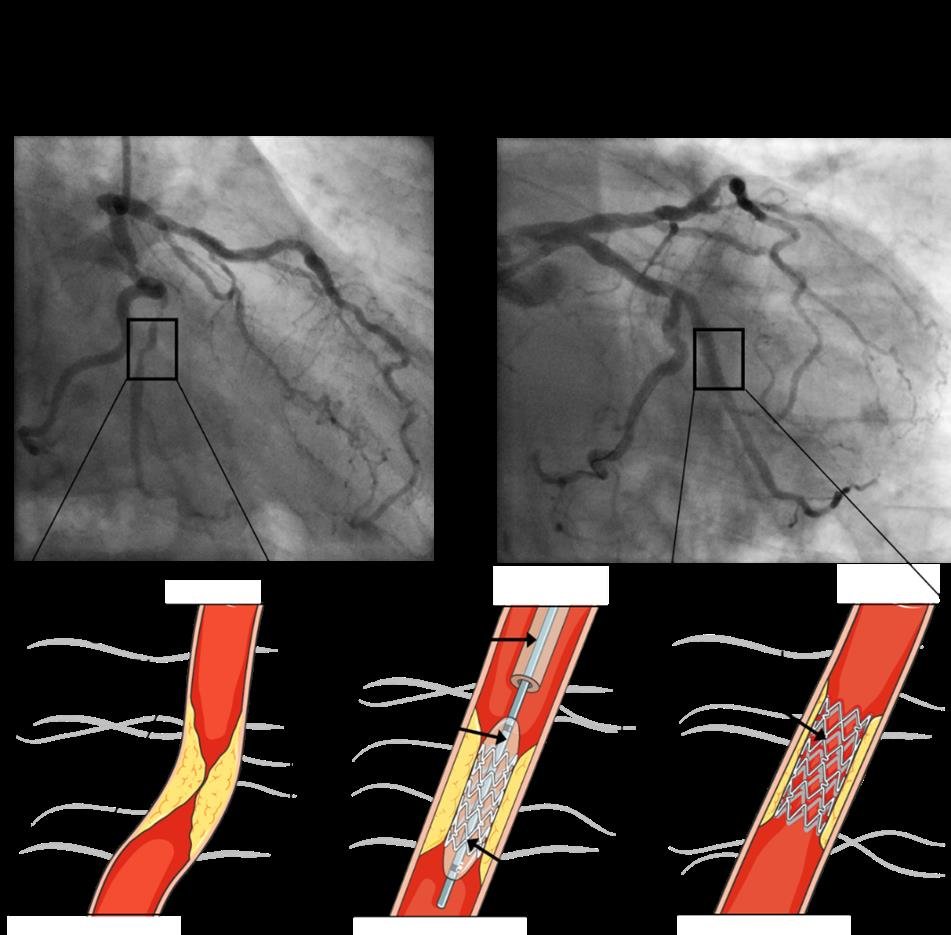

Despite significant advances in diagnosis and management, coronary artery disease remains a significant worldwide cause of morbidity and mortality, particularly in older adults, with a steep increase in mortality in those aged ≥70 years old.1-3